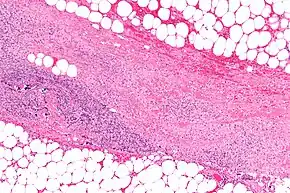

Micrograph of necrotizing fasciitis, showing necrosis (center of image) of the dense connective tissue, i.e. fascia, interposed between fat lobules (top-right and bottom-left of image), H&E stain